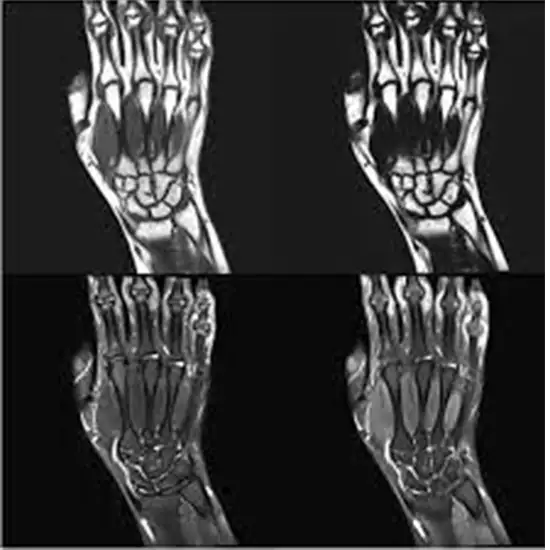

An MRI of the Right Hand with Contrast shows the hand's bones, joints, cartilage, tendons, ligaments, muscles, and blood vessels. The contrast improves the MRI's sensitivity and diagnostic accuracy by making inside organs more visible.

This test is given to look for signs of arthritis, degenerative changes, or dislocation of the joints of the hand. It is also used to check for broken bones in hand.